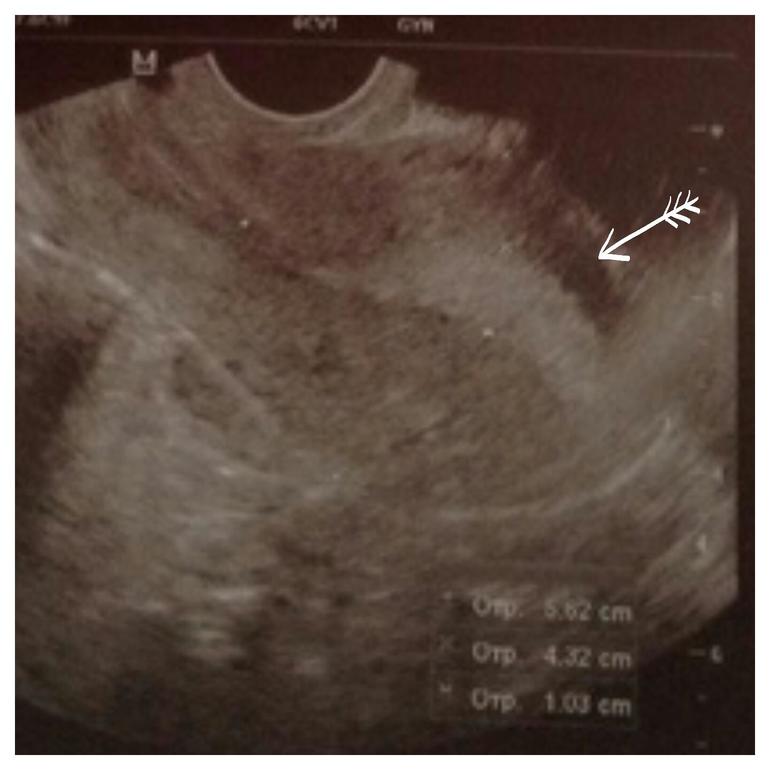

Дальше... Что это за анэхогенное включение в матке? Это может быть миома? Или что это? Вот про это включение она мне ни слова не сказала, а увидела я уже когда в машине протокол стала читать. Ну и киста на шм. Короче, вообще ниче непонятно... Сказала половой покой и вообще покой.....

На ПЯ похоже это ваше анэхогенное образование. В самом дне матке как раз. И ЖТ шикарное! Может сдадите кровь на хгч?

На втором фото! Прямо в дне матки!!!!!

Аааа, вижу что то полукруглое... Такое большое.. Спасибо

И вроде не в эндометрии а в миометрии... т.е в мышечном слое матки... как и в шейке... эндометриоз никогда не ставили пож вопросом?